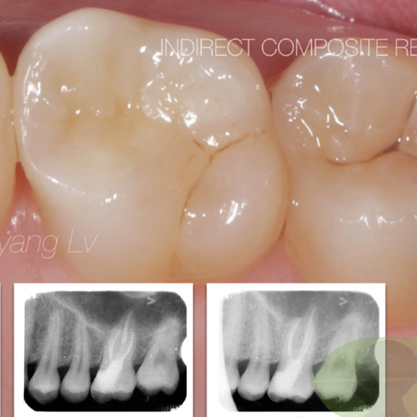

• 根管修復(fù)

產(chǎn)品評(píng)價(jià)和臨床案例

八顆牙用戶(hù)使用心得交流分享